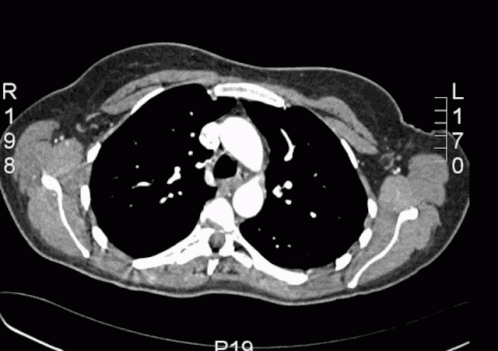

1. Существа иной размерности. С нашим пространством пересекаются лишь отчасти. Выглядят как мерцающие бесформенные пятна. Что-то вроде обьемного скана КТ. Живут внутри черных дыр.